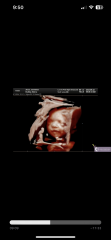

3d scan and her eyes look far apart??

I had a 3d ultra sound a few weeks ago at 26 weeks and 5 days. I have been so stressed out that her eyes look far apart and maybe the missed something? Please let me know what you think. I’m not sure if it’s because she still has time to grow into her face or maybe the pictures aren’t the best?? Idk but I’m very stressed out

Hi, @Spiritnlili1 and congratulations on your pregnancy. I think most 3d scans look a little 'off' in some ways - they're building a 3d image through layers of skin, muscle, fat and liquid, of a small baby that's still developing and that moves. My DC kind of looked like an alien on their scans but they're pretty cute in reality. Your baby looks just perfect for 26 weeks!

No i would say this baby looks perfect. congrats! :-)

Just looked at our 3D scan out of interest and his eyes were further apart than your ones - didnt notice at the time but it does look weird 😂they dont come out like that!